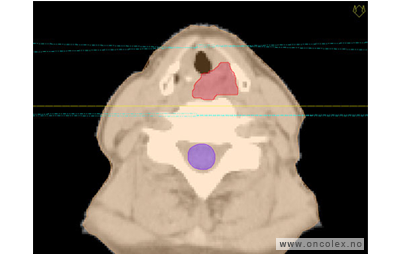

Skisse over hvordan strålefeltet planlegges:

Illustrasjon for målvolum

• GTV (Gross Tumor Volume): Identifisert tumor.

• CTV (Clinical Target Volume) GTV + omkringliggende vev hvor det kan væremikroskopisk spredning.

• ITV (Internal Target Volume): CTV + en indre margin som tar hensyn tilindre bevegelser og endringer av CTV.

• PTV (Planning Target Volume): Innstillingsmargin som inneholder ITV og samtidig tar hensyn til antatte pasientbevegelser, samt variasjoner i pasientopplegging og feltinnstillinger.

• Feltgrense. Tegnes som oftest på kroppen.

ICRU (International Commission on Radiation Units and Measurements)